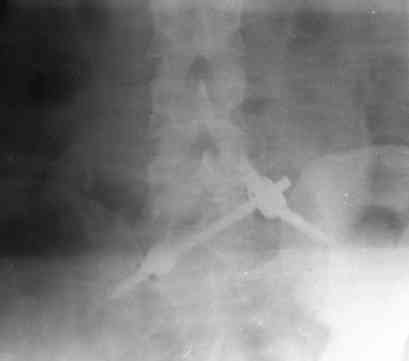

Уважаемые коллеги! На днях оперировал перелом таза месячной давности - разрыв симфиза, перелом обеих ветвей правой лонной кости, трансфораминальный перелом крестца слева. Представляю рентгенограммы с задержкой - технические причины.

Предоперационные рентген и КТ, в операционной - снимки после каждого фиксатора. Вертикальное смещение полностью устранить не удалось. В первую очередь за счет заднего полукольца. Хотя при компрессии на стержнях горизонтальное смещение было сантиметра 1,5. Т.е. крестец, на мой взгляд еще не сросся. От коллег хотел-бы услышать допустима-ли такая остаточная деформация?